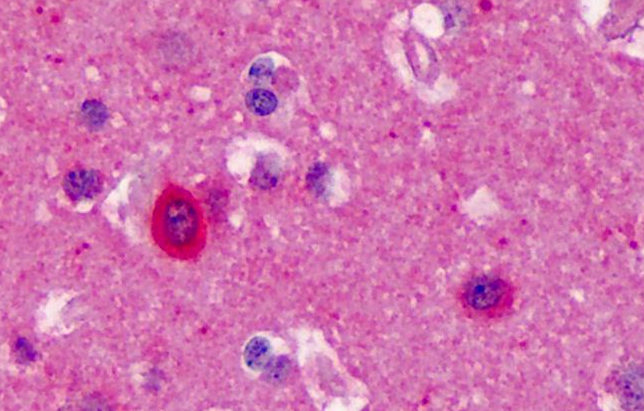

Immunohistochemical staining of mouse caudate-putamen using NOS1 antibody

Immunohistochemical staining of Human Cortex using NOS1 antibody